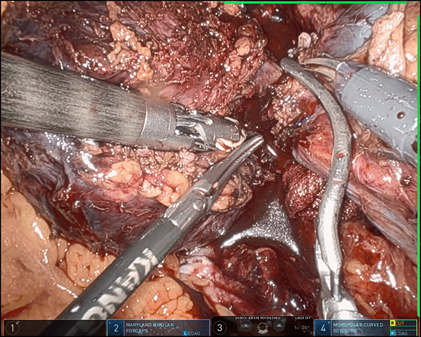

10. 完整切除肿物,装入标本袋,扩大切口取出标本。探查创面无明显活动出血,可见肿瘤位置在十二指肠、肾静脉之间,移除后关系更能一目了然(如上图)。创面填止血纱,留置引流。